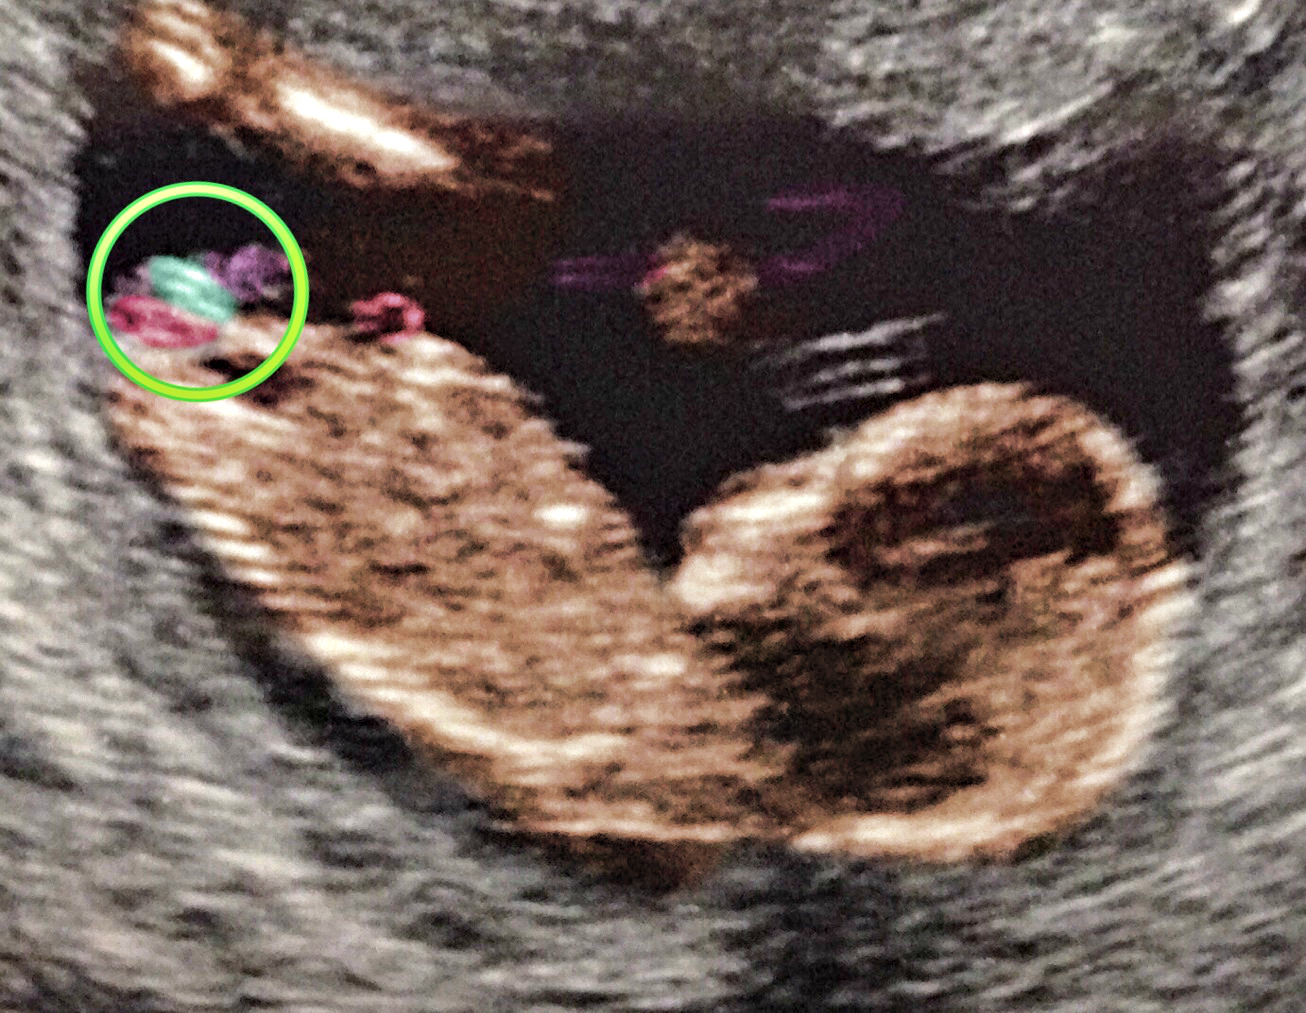

Nope you are totally right on your labeling. The cord is in purple which runs behind and in between the legs where the mess of a gender is LOL It also looks from the "scratch marks" up by the head (hand movement) youve got quite the mover and baby is just about to roll so that really flubs up the angle. Im more inclined to go with girl because of the way it looks but just cant be sure because of the rotation plus cord. Depending on the movement either the part in pink is correct and girl or the part in blue is correct and boy. All that cord and movement this one is already trouble from the start HAHA! Attachment 23638